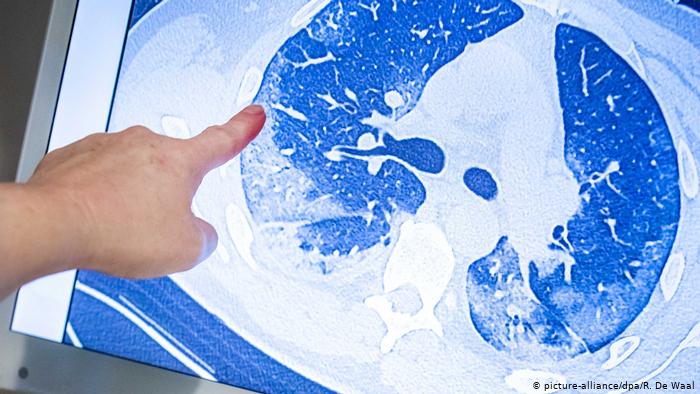

لماذا يفضل "كرورنا" الرئتين عن بقية أعضاء الجسم؟

كشفت دراسة اسبانية حديثة، أن البروتينات الموجودة في الرئتين، هي المفضلة بالنسبة لفيروس كورونا، لانها تعمل كمنشطات أساسية له، وجد فريق البحث، من جامعة سرقسطة، أن بروتينات الرئتين تستجيب لمحفزات يطلقها الفيروس، وبالتالي تصبح أكثر عرضة للإصابة.

ويستخدم الفيروس بروتينا موجودا في الجزء الخارجي من الخلايا، يسمى الإنزيم المحول للأنجيوتنسين 2 (ACE2)، لدخولها وإصابتها. وبمجرد دخول الخلية البشرية، تتفاعل البروتينات الفيروسية مع تلك الموجودة في الجسم.

وقال المعد الرئيس الدكتور إرنستو إسترادا، الأستاذ بمعهد الرياضيات التطبيقية في الجامعة، إن "هذا البروتين، المستقبل موجود في في معظم الأعضاء البشرية، لكنه يتركز بشكل اكبر ي الرئتين، ومع ذلك، فإن الفيروس يصيب بعض الأعضاء بشكل انتقائي وليس كلها، كما هو متوقع من هذه الآليات المحتملة.

وأوضح إسترادا أن هناك 59 بروتينا داخل الرئتين، تعمل كمنشطات أولية للأعضاء الأخرى.وعندما يؤثر الفيروس على الرئتين، فإن هذا يؤدي إلى سلسلة من الأحداث التي تؤدي إلى تغييرات في البروتينات ضمن الأعضاء الأخرى. ومع ذلك، فإن هذه التغييرات تحدث فقط في أعضاء معينة، مثل القلب والكلى وليس في أعضاء أخرى، مثل المعدة.

وأوضح أن استهداف بعض هذه البروتينات في الرئتين بالأدوية الموجودة، سيمنع اضطراب البروتينات التي يُعبّر عنها في أعضاء أخرى، وتجنب فشل العديد من الأعضاء، والذي يؤدي في كثير من الحالات إلى وفاة المريض.